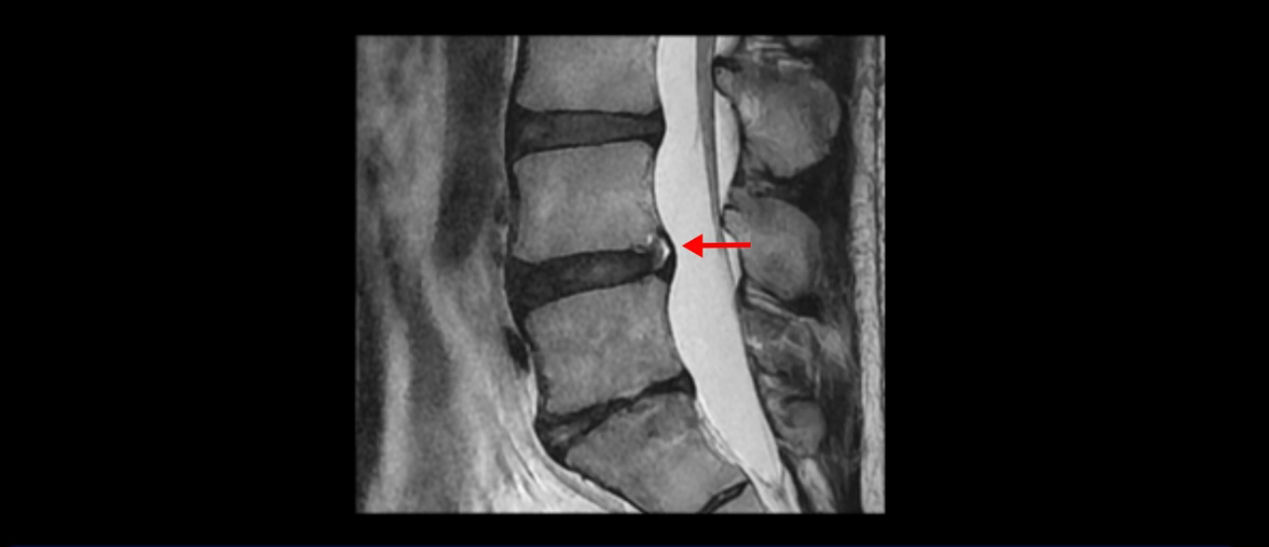

그런데 이분의 증상과 MRI가 전혀 일치하지 않는데, 왜 그런지 지금부터 자세히 설명드립니다. 이분 증상은 앉으면 엉치와 허리가 심하게 아파 10분 이상 앉는 게 어렵고 양쪽 발가락이 앉아있을 때나 누워있을 때 다 저립니다. 걸을 때도 아파서 10분 걷기도 어렵습니다. MRI를 마디마디 살펴보면 1번 2번은 오른쪽으로 살짝 밀려나온 디스크가 있지만 전혀 심하지 않고, 뒤에 또 설명하겠지만 최근에 밀려나온 급성 디스크가 아니고 오래된 디스크로 판단됩니다.

5번 1번 역시 가운데로 디스크 조금 밀려 나와있지만 신경 공간 넓이는 아주 넓어서 신경 눌림 있을 거라고 예상이 안됩니다.

앞서 1번 2번, 4번 5번, 5번 1번의 디스크가 찢어지고 조금 밀려 나온 게 최근에 찢어진 게 아니고 오래된 걸로 보인다고 말씀 드렸죠. 왜 그럴까요? 만약 급성으로 찢어진 것이라면 아주 심한 디스크성 통증이 있겠죠. 기침이나 재채기를 하면 심하게 아프고 허리를 조금만 구부리거나 비틀면 아주 날카로운 통증들이 생길 겁니다. 그런데 이분은 이런 증상이 전혀 아닙니다. 또 디스크의 밀려나온 정도도 전혀 심하지 않기 때문에 이분이 가지고 계신 양쪽 다리 저림, 특히 이분은 누워있을 때도 양쪽 발이 발가락까지 쑤신다고 하는데 이정도 디스크 때문에 그런 증상은 생길 수가 없는 겁니다. 이처럼 이분의 가벼운 디스크 탈출은 이미 오래 전에 진행되었고 섬유륜 자체는 이미 아문 상태인데도 디스크내장증을 진단받은 환자들 중에는 본인이 섬유륜 파열 환자라고 끝까지 믿는 분들이 많습니다. 다시 말하지만 디스크내장증이라는 진단을 받은 환자들을 보면 거의 전부 다 섬유륜 파열 증상이 아닙니다. 증상이 완전히 다릅니다. 진단이 애초에 잘못되면 어떤 치료를 받아도 좋아질 수 없습니다.